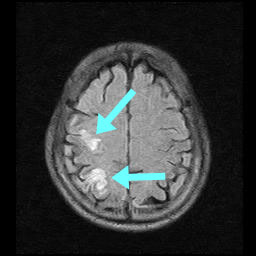

多発性脳梗塞